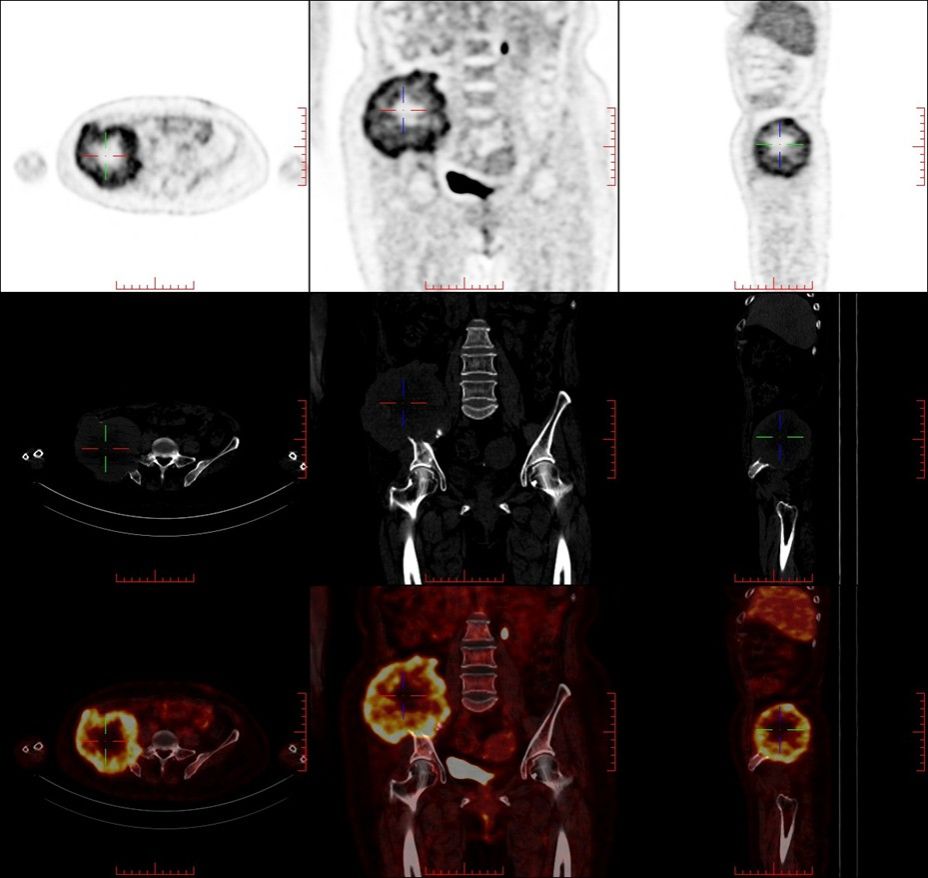

患者因持续加重的髋部疼痛、活动受限就医,经我院详细检查,确诊为骨盆巨大肿瘤。影像学显示,这个巨大占位不仅侵犯了右侧髂骨、部分骶骨及周围软组织,更紧密包绕了重要的血管神经丛。骨盆区域解剖结构异常复杂,血供丰富,神经密集,历来是外科手术的“高危雷区”。如此巨大的肿瘤,完整切除同时保护关键结构、控制致命性出血、维持骨盆稳定性的难度堪称“登峰造极”。

面对这一严峻挑战,我院迅速集结了脊柱骨肿瘤科、普通外科、血管外科、麻醉科、手术室、重症医学科、输血科、病理科及影像科的权威专家,成立专项治疗组。团队依托先进的3D打印技术,精准复制患者骨盆模型,进行手术模拟预演;利用术中神经电生理监测、先进的影像导航等尖端设备,为手术保驾护航;并制定了详尽的血管控制预案、大出血应对方案及骨盆功能重建策略。